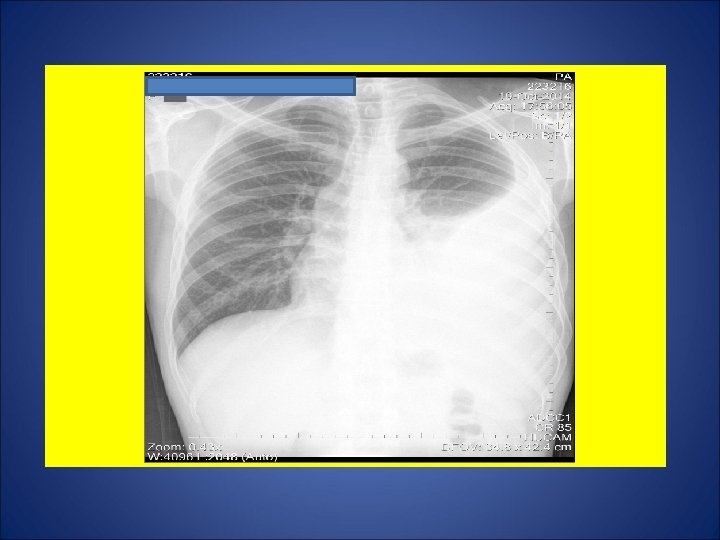

CASO 3, feminina, 25 anos de idade, agente administrativa numa creche. Tosse discreta não produtiva durante os dois últimos meses. Há 1 mês, adinamia. Há 1 semana, febre e sudorese. Durante os últimos 15 dias, perda de 5 Kg. Na madrugada de 09 julho 2014, acordou com tosse seguida de vários episódios de hemoptise. Avaliada por um otorrinolaringologista, sendo prescrito antibiótico 1 cp/dia por 5 dias. Remissão gradual da hemoptise durante os próximos dias. Persistência de tosse discreta. A partir de 21 set 14, surgimento de dor de garganta e disfonia. Negou episódios de escarros hemoptóicos ou hemoptise. A partir de 8 out 14, recidiva da tosse seguida de vários episódios de hemoptise. Foi referenciada para pneumologista, sendo solicitado radiografia de tórax e pesquisa de bacilos álcool ácido resistentes. Negou contato com casos de tuberculose. Negou tuberculose prévia. Negou tabagismo e etilismo. HIV negativa. Ex. fisico: P=73 Kg, Altura= 1, 63 m, IMC= 27, 47, FC = 110 bpm. Tem marca de BCG em MSD.

ESCARROS ESPONT NEOS: 1º) 17/10/14: 10 m. L – MUCOPURULENTO – 10 min: BAC 1+ – CULT em curso 2º) 20/10/14: 10 m. L – SALIVA – 20 min: BAC NEG – TRM M. tuberculosis - CULT em curso 3º) 20/10/14: 10 m. L – SALIVA – 15 min: BAC 2+ – CULT em curso 4º) 21/10/14: 12 m. L – MUCOPURULENTO – 30 min: BAC NEG – CULT em curso